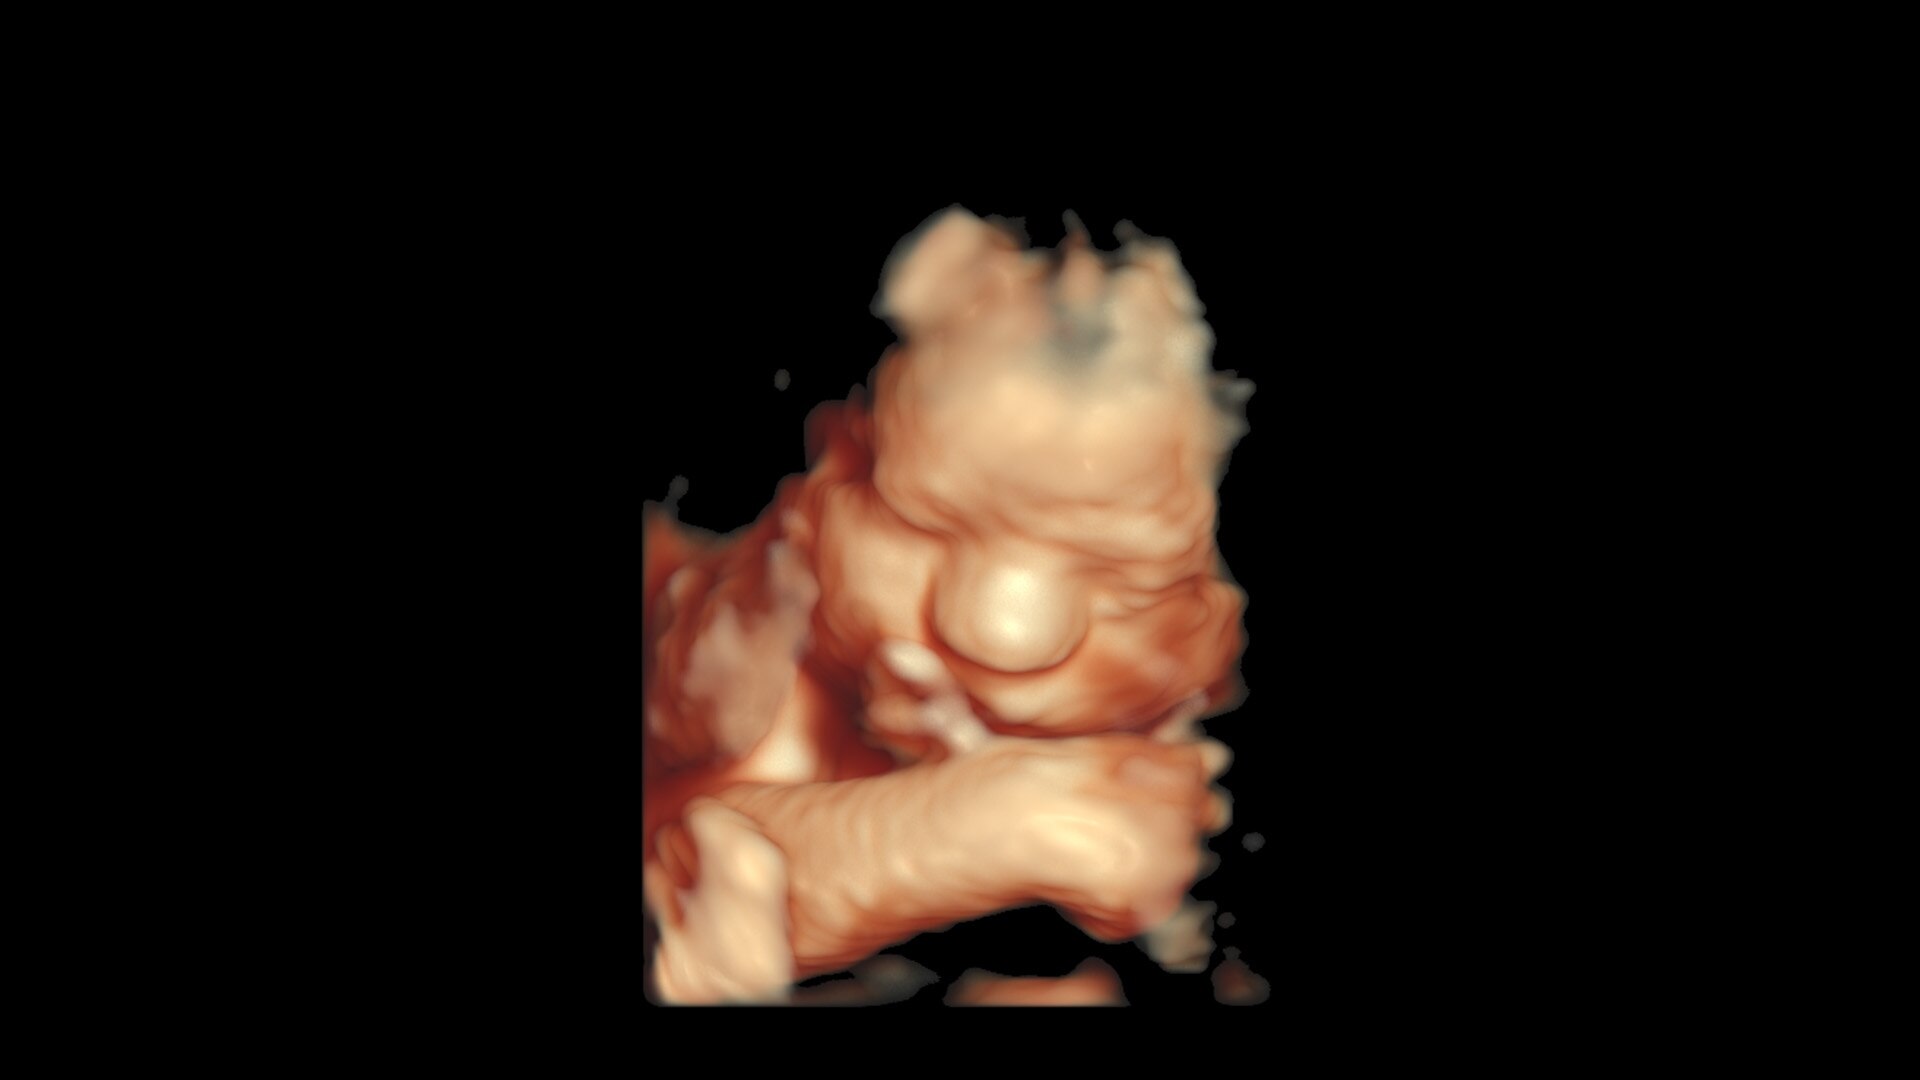

Whizz RenderLive and V-Live 2.0

Support OB scanning with faster 3D/4D rendering and capture incredible static 3D/4D imaging